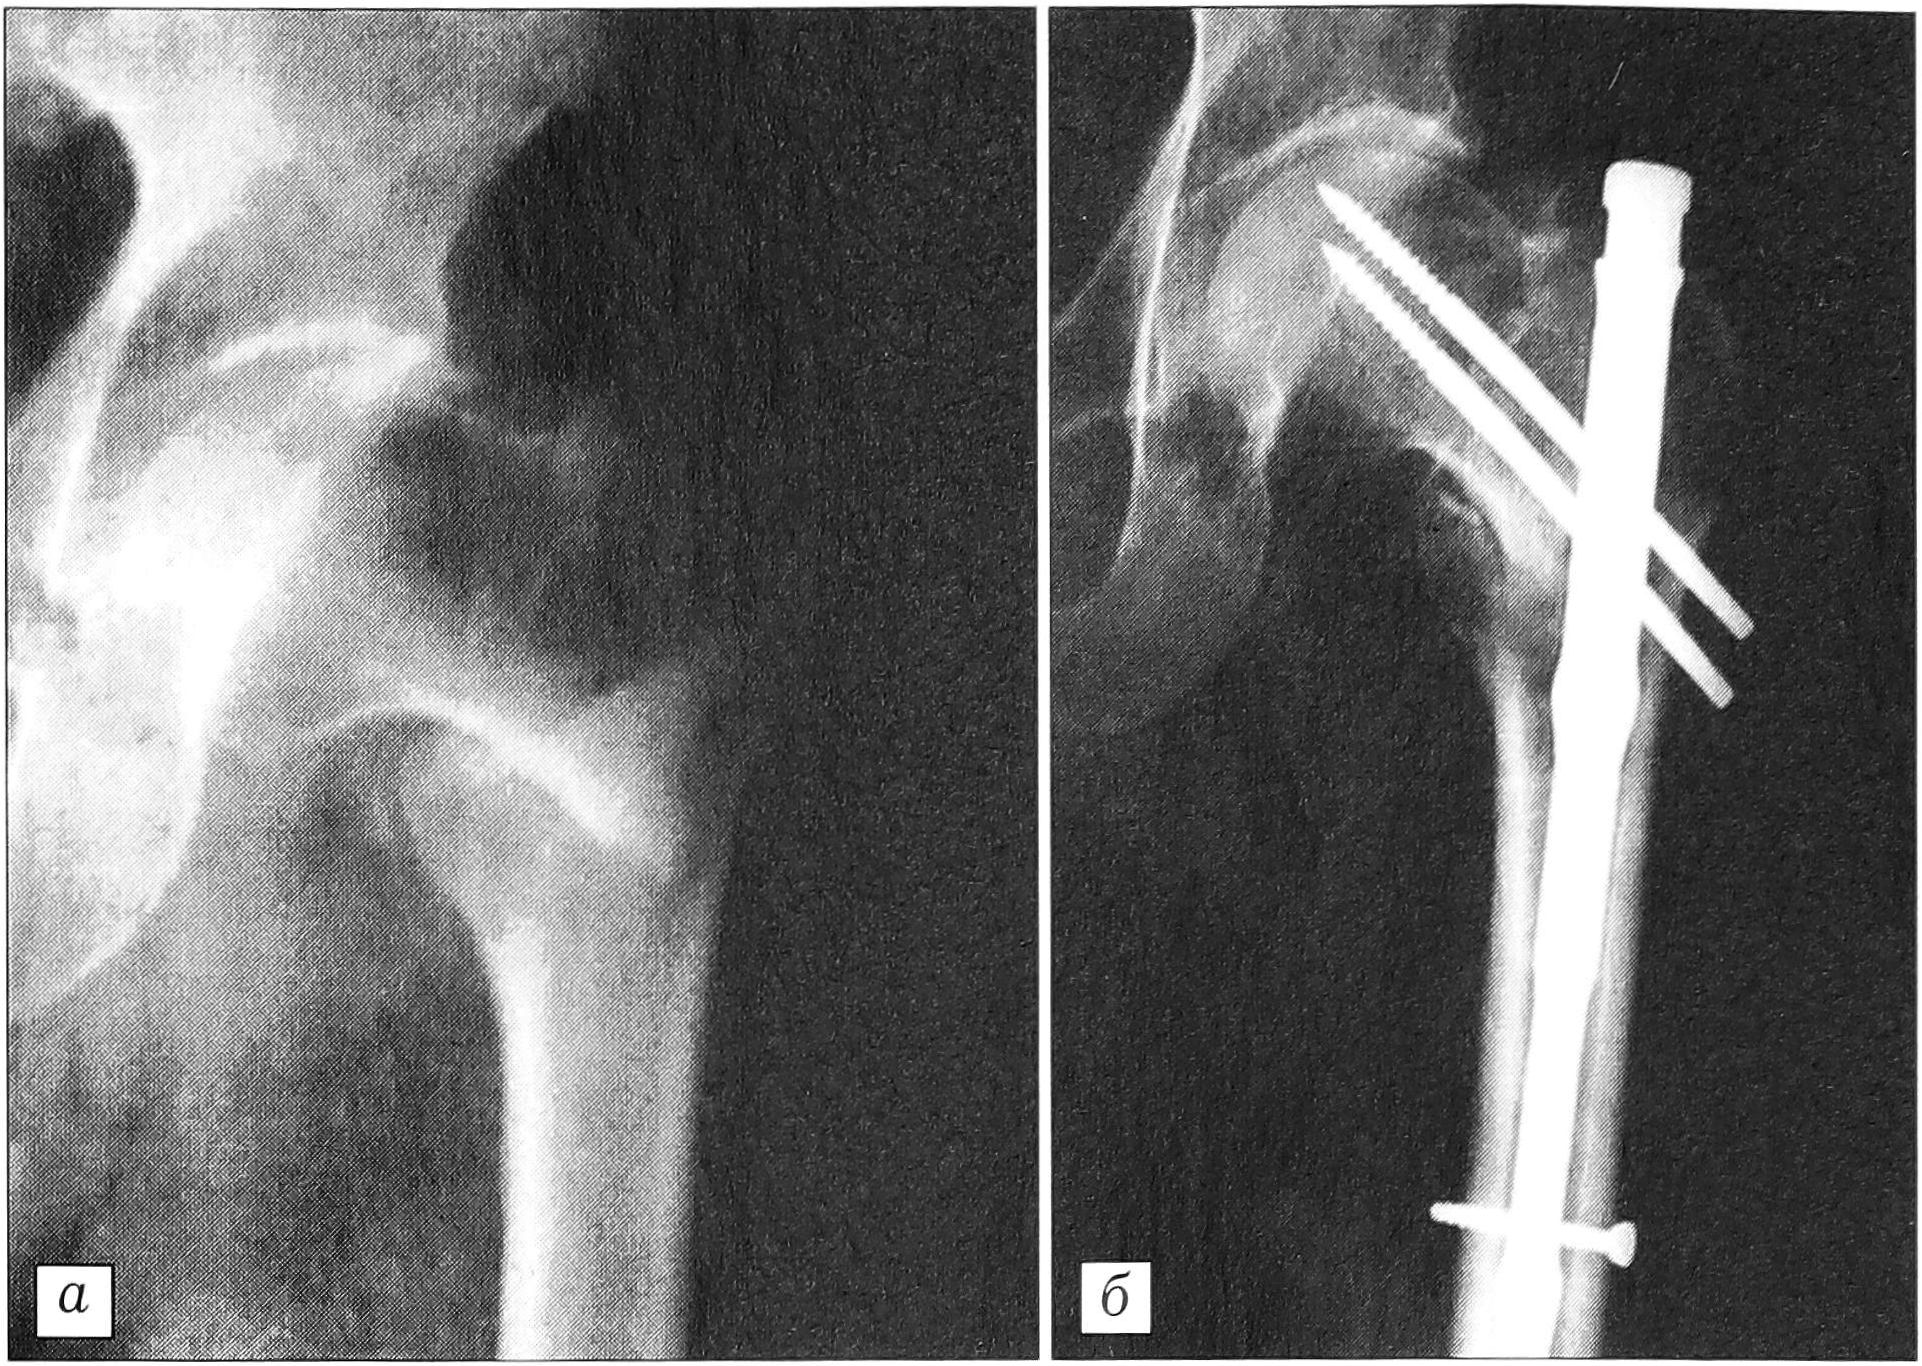

Больной Н ., 1920 года рождения, поступил в травматологическое отделение 22.05.99 с диагнозом: закрытый чрезвертельный перелом левой бедренной кости со смещением отломков — 3.1.А1/2 по классификации АО (рис. 2, а). Травму получил в результате падения на улице. 24.05.99 произведена операция — закрытый остеосинтез левой бедренной кости при помощи БМПФ-7 по разработанной методике. Послеоперационный период протекал без осложнений. Через 7 дней после операции пациент выписан на амбулаторное лечение. Частичная нагрузка оперированной конечности начата через 1 мес после операции, полная — через 2,5 мес. Осмотрен через 3,5 мес: двигательная и опорная функция конечности полностью восстановлены, рентгенологически — перелом сросся с полным восстановлением анатомии проксимального конца бедренной кости (рис. 2, б).

Рис. 2. Рентгенограммы больного Н. при поступлении (а) и через 3,5 мес после операции (б).